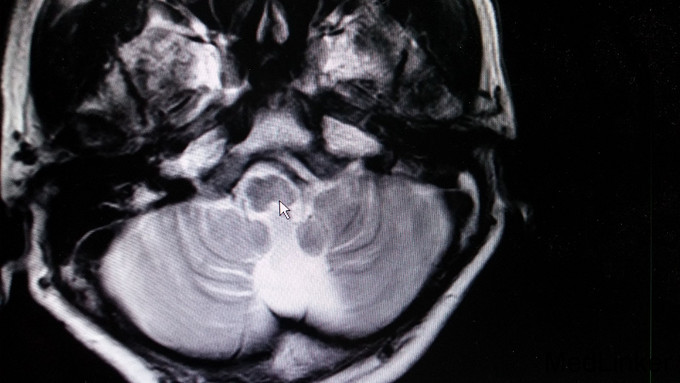

患者,男,62岁,患者因“行走不稳10年余,渐进性加重伴言语不清2年余”入院。10余年前无明显诱因下出现行走不稳,与当地医院就诊,行颅脑磁共振提示小脑萎缩,随后间断服药治疗,行走不稳未见改善,并逐渐加重,双上肢持物不稳,2年余前开始出现言语不清,行走及站立时双下肢乏力、不稳,进食可出现呛咳,于湖南湘潭医院拟“小脑性共济失调”治疗,治疗效果不明显,今患者进一步诊治。否认家族中类似病史。

构音欠清,双眼外展活动受限、悬雍垂左偏,左侧咽反射减弱,双下肢肌力4级,共济失调。辅查: 1. 头颅MRI:小脑萎缩,桥脑、延髓体积偏小,注意变性疾病(橄榄桥脑小脑萎缩)可能; 2. 肌电图:神经性损伤;诱发电位:双上下肢体和双侧视觉异常体感诱发电位。